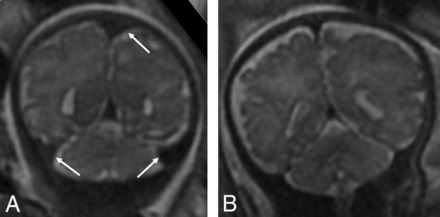

Findings recorded on the fetal MR imaging were germinal matrix hemorrhage, the presence of restricted diffusion when performed, ventriculomegaly, and enlarged extra-axial spaces. Enlargement of the extra-axial spaces was determined when the distance between the inner margin of the calvaria and the frontal or parieto-occipital region was greater than the values for gestational age.8,9 Ventriculomegaly was diagnosed when the maximum width of the lateral ventricles at the level of the atrium measured >10 mm.10 The presence of maturational delay, engorged dural venous sinuses, and parenchymal signal abnormality was recorded by a senior neuroradiologist (B.M.K.-F.). Brain maturation was assessed comprehensively on T2-weighted images by comparison with a published and widely used timeline of brain development, germinal matrix involution, myelination, and cortical infolding/sulcation.11 Brain maturation was dichotomously graded as normal or delayed. Figure 1 highlights a few of the maturational changes that were assessed.

A, Coronal T2-weighted image of a fetus with CDH at 24 weeks demonstrating expected maturation with the presence of the interhemispheric and Sylvian fissure (dashed arrow), but with an otherwise smooth appearance of the frontal lobes. There is expected visualization of the migrating neurons as evidenced by alternating dark and bright bands in the cerebral parenchyma (arrows) corresponding, from inside out, to the ventricular zone/germinal matrix, periventricular fiber rich zone, intermediate zone, subplate zone, and cortical plate. B, Coronal T2-weighted image of a 32-week fetus with CDH showing age-appropriate maturation with the presence of the superior and inferior frontal sulci (arrows) and the inferior temporal sulcus (dashed arrow). The 5 layer pattern of migration is no longer present.